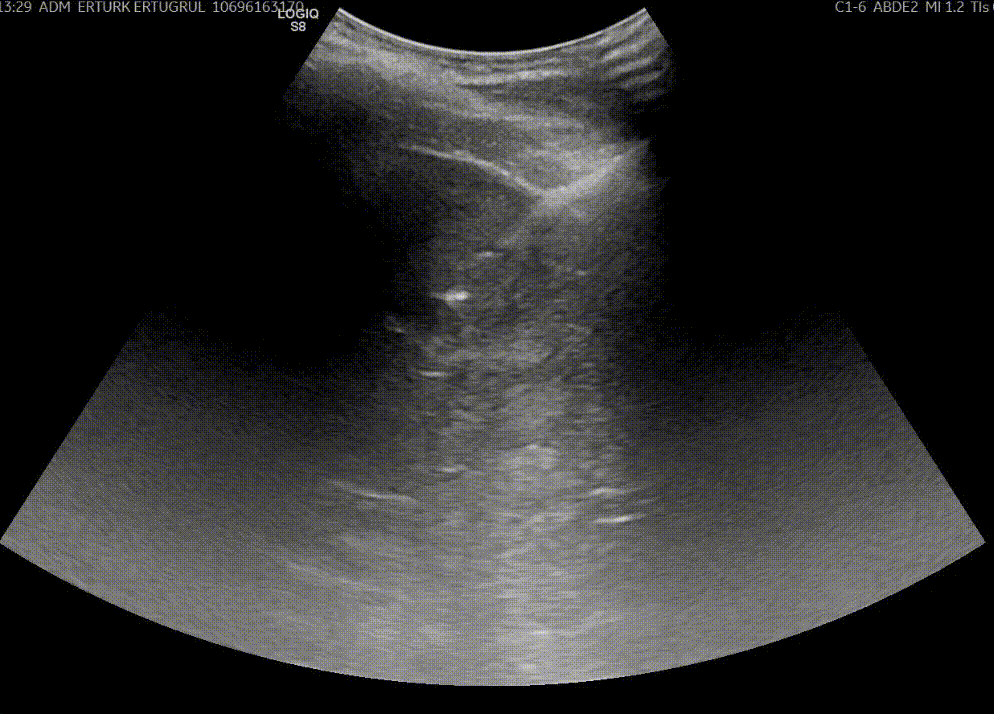

Girişimsel Onkoloji, kanser tedavisinde minimal invaziv yöntemleri kullanan, tıbbın hızla gelişen multidisipliner bir dalıdır. Bu yöntemler genellikle radyoloji ve görüntüleme teknikleri (ultrason, BT, MR, anjiyografi vb.) eşliğinde uygulanır.

- Radyofrekans Ablasyon (RFA): Kanserli dokunun yüksek frekanslı radyo dalgalarıyla yakılarak yok edilmesi.

- Mikrodalga Ablasyon (MWA): Mikrodalga enerjisiyle tümör dokusunun ısıtılarak ortadan kaldırılması.